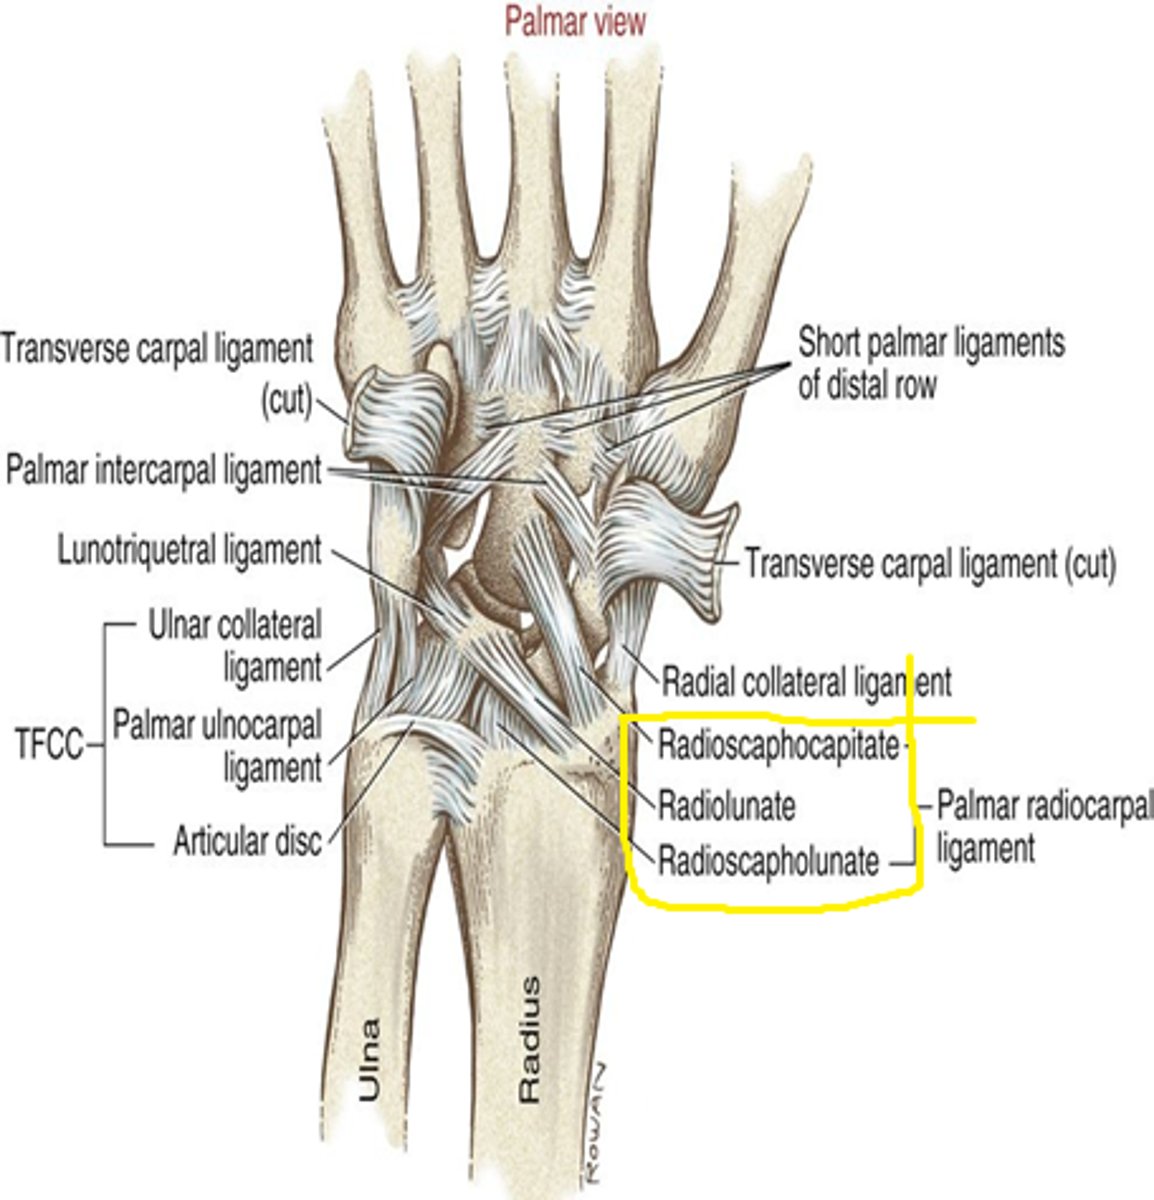

palmar radiocarpal ligament

ligament running from the anterior surface of the distal radius to the anterior surface of the carpal bones

Thick 'sling-like' ligament complex that covers almost the entire volar joint capsules of the

radiocarpal and midcarpal joints

Tightens in wrist extension

radial collateral ligament

Connects scaphoid to radial styloid

Limits ulnar deviation

ulnar collateral ligament

Connects triquetrum to ulnar styloid

Limits radial deviation

Palmar radiocarpal ligaments are much ________ and _________ than its dorsal counterpart

thicker; stronger